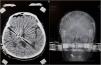

Hemiballism/hemichorea (HH) is a hyperkinetic movement disorder observed mostly in older adults with cerebrovascular diseases. Although the symptoms improve without any treatment, lesioning or DBS (deep brain stimulation) may be rarely required to provide symptomatic relief for patients with severe involuntary movements. HH is a rare complication of uncontrolled diabetes. There are only a few reported cases of diabetic HH that have been surgically treated. Thus, herein, we have reported the case of a 75-year-old female with type-II diabetes mellitus that presented with disabling involuntary limb movements of the left side, despite being treated conservatively for six months. DBS targeting the globus pallidus internus (GPi) and ventral intermediate (Vim) thalamic nucleus was performed. Complete resolution of symptoms was achieved with a combined stimulation of the thalamic Vim nucleus (at 1.7 mA) and GPi (at 2.4 mA). The combined stimulation of the Vim nucleus and GPi effectively resolved the diabetes-induced HH symptoms in our patient. Thus, although certain conclusions cannot be drawn due to the rarity of the surgically treated patients with HH, the combined stimulation is a novel treatment option for resistant HH.